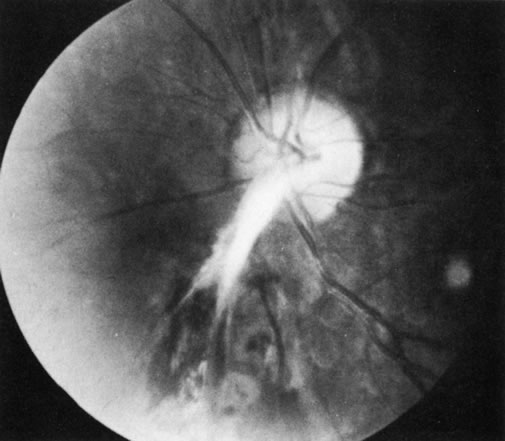

The Vogt-Koyanagi-Harada syndrome (VKHS) is a chronic, bilateral, exudative uveitis associated with whitening of the hair and eyelashes (Fig. 8), vitiligo, and meningeal irritation. It is a combination of two overlapping disease entities. VKHS is a severe anterior-segment inflammation associated with dysacousia, vitiligo, alopecia, and poliosis. Harada's disease is limited largely to posterior uveal inflammation with serous retinal detachments, disc involvement, meningeal inflammation, and sometimes skin and hair changes (Figs. 9 and 10). Because the symptoms of the two diseases overlap significantly and their histopathologic features are similar, the two are now regarded as a single disease entity.

Fig. 8. Poliosis in Vogt-Koyanagi-Harada syndrome. (Courtesy of F.I. Proctor Foundation.)

Fig. 9. Optic nerve involvement in Vogt-Koyanagi-Harada syndrome. (Courtesy of Dr. R. Weinberg.)

Fig. 10. Posterior involvement in Vogt-Koyanagi-Harada syndrome with pigmentary changes and scarring. (Courtesy of Dr. R. Weinberg.)